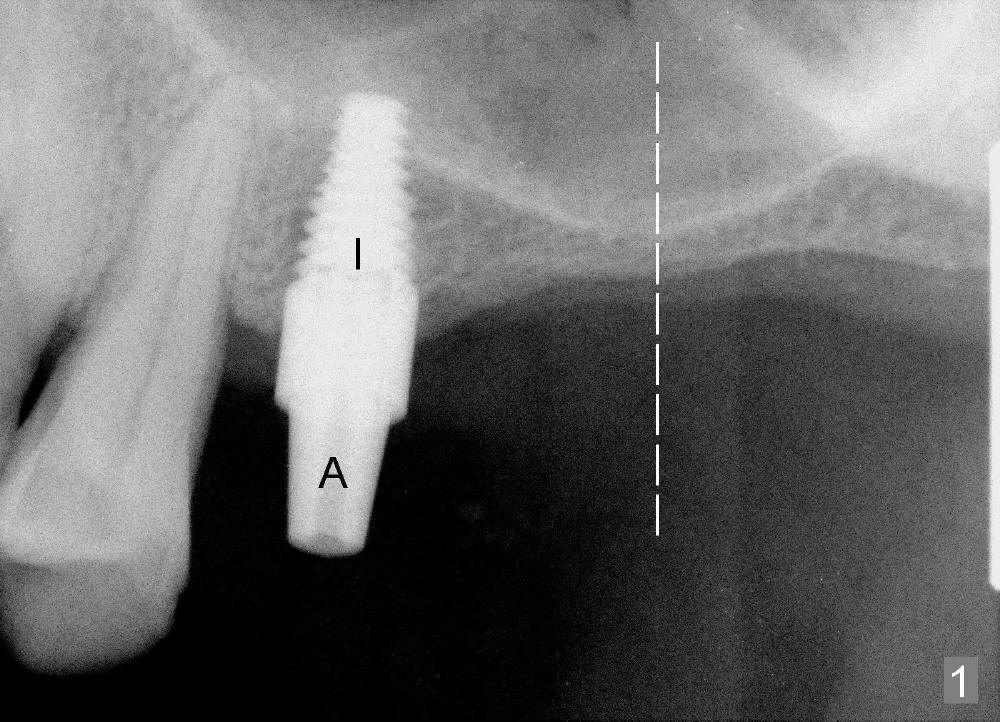

A 53-year-old man is afraid of pain. It is hard for him to have the first implant (Fig.1 I: 4.5x11 mm) placed at the site of #13 with sinus lift from the crestal approach. An abutment is placed immediately (A: 3.5 mm 0º), followed by an immediate provisional. The 2nd implant to be placed is at the site of #14 with 2 mm bone height (Fig.1 dashed line area). It appears that sinus lift should be done with lateral window approach.

Fig.2 is a CBCT coronal section at the site of #14, as indicated by the dashed line in Fig.1. The arrowhead (<) denotes the anterior bony wall of the maxillary sinus, whereas the arrow (->) the sinus membrane.